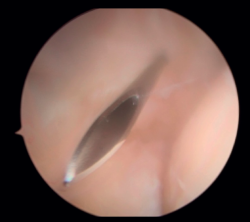

En primer lugar, se realiza el portal anteromedial de visión, incidiendo únicamente la piel y realizando disección roma con un mosquito recto. A continuación, se introduce la vaina del artroscopio, atravesando de forma anterior y proximal el septo fibromuscular medial, en dirección a la cabeza del radio, de forma posterior y distal, para evitar lesionar el nervio cubital y el paquete vascular anterior del codo. Una vez introducida la óptica en el portal medial, se procede a realizar el portal lateral proximal como portal de trabajo. Se realiza bajo visión directa, utilizando como guía una aguja intramuscular de fuera a dentro, para localizar el punto de entrada que permita mejor ángulo de trabajo (Figura 4). Posteriormente, se incide en la piel y se realiza disección roma con un mosquito recto para entrar en la articulación (Figura 5).

Figura 4. Posicionamiento con aguja del portal lateral (paciente en decúbito lateral, codo derecho, visión desde el portal medial).